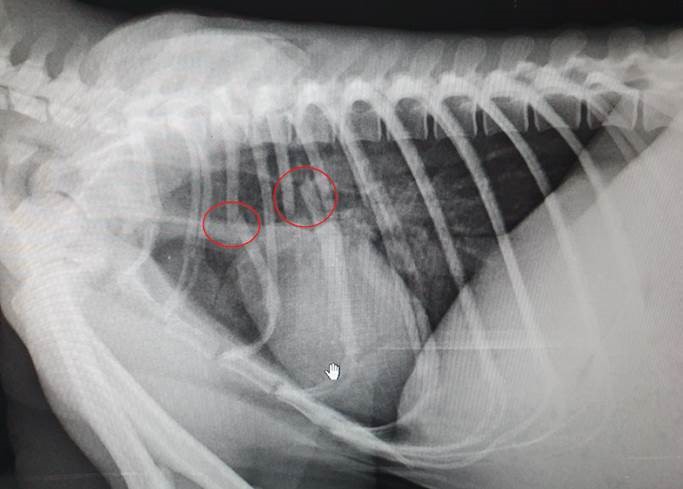

However, vets would soon discover Fluffy had an internal tear in her chest wall, a collapsed lung, broken ribs and extensive bruising. Despite that, she was still carrying Andy on her back.

"Her injuries were so severe we didn't expect her to survive, but incredibly Fluffy pulled through following emergency surgery to repair her chest. She is one tough koala."